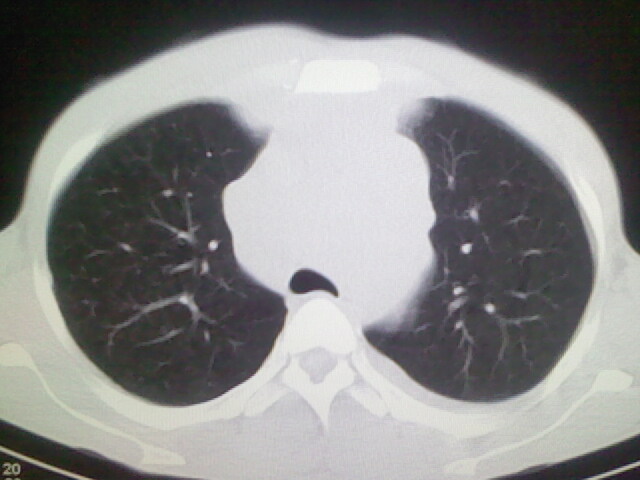

以下是引用杀毒软件在2008-9-3 6:11:00的发言:[br]侵袭性胸腺瘤------一般不侵到气管旁[br][br]考虑----纵隔淋巴瘤,心包及胸膜受累

以下是引用随光逐影在2008-9-3 7:07:00的发言:[br]1)考虑淋巴瘤可能。2)双侧胸腔积液(以左侧为甚)。3)心包积液。